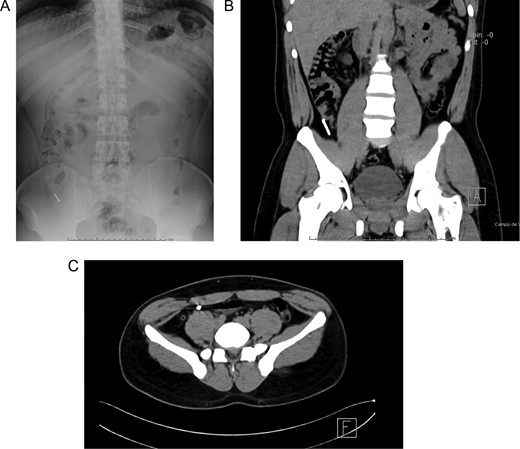

Patient is a 27-year-old male without past medical history. During his annual routine medical examination, an abdominal X-ray was requested. A metallic foreign body (30 mm nail) was discovered in his lower right abdomen (Fig. 1A). With these findings, he was transferred to our hospital. On arrival, he was completely asymptomatic, and he had no recollection of having swallowed the nail. Abdominal examination was unremarkable, and he had no evidence of any surgical scars. With these findings, a contrast-enhanced abdominal computed tomography (CT) revealed the presence of a 30 mm metal nail inside his appendix (Fig. 2A). The appendix had an outer diameter of 5 mm and was surrounded by homogeneous, non-inflamed fat and contained intraluminal air (Fig. 3A). A colonoscopy was requested to assess the cecum to try to remove the foreign body, however, after reaching the cecum and the appendix the nail could not be found (Fig. 1B). An intraoperative abdominal x-ray was needed, which confirmed the presence of the nail in the appendix (Fig. 2B).

(A) Colonoscopy, the appendiceal orifice is seen without the foreign object. (B) Intraoperative abdominal x-ray confirming the presence of the nail in the appendix. (C) Appendix during surgery.

In this context, a surgical approach was needed to assess the appendix and the cecum wall. After a Rocky-Davis incision, the appendix was exposed and an object of hard consistency was found at its tip (Fig. 3B). The surgical decision was straightforward, the appendix was resected, and the surgery was completed without complications (Fig. 1C).

After this, the appendix was dissected and a 30 mm nail was found inside its lumen (Fig. 2C and Supplementary Video).